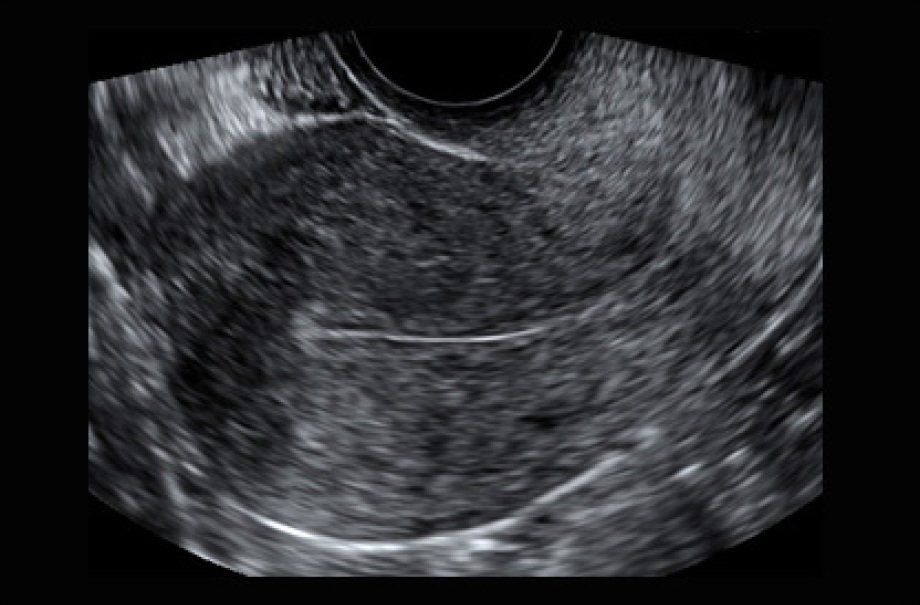

- Escaneo transvaginal

- El escaneo proporciona imágenes detalladas que ayudan a determinar si los órganos pélvicos son normales o tienen anormalidades como:

- Fibromas

- Pólipos endometriales

- Quistes ováricos

- Endometriosis

- Ovarios poliquísticos